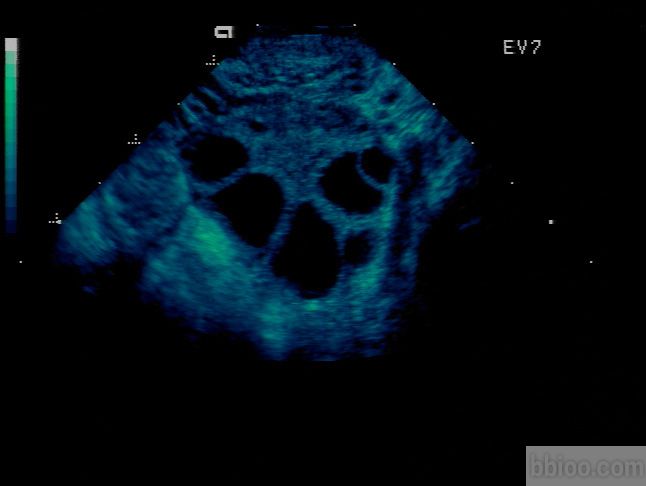

卵巢最主要的功能就是产生卵子,卵子在卵泡李和卵泡同步成熟,优生优育的基础就是发育良好的卵子。但是卵子太小,肉眼不可见,只能间接的通过视察卵泡来推测卵子的发育情况。B超检查是最直观最简单的评估办法,每个周期通过3~4次的阴道B超监测,可以视察到有没有正常的卵泡生长、发育、排出。

卵泡的大小在一定程度上反映出卵子的发育程度,可以用来预测排卵期以及最后的受孕几率。但是,我们能看到的仅仅是卵泡而不是卵泡当中包含着的卵子。成熟卵泡的直径是17~24mm,而卵子的直径在0.2mm左右,超声上是无法发现的。因此卵泡的大小并不能完全代表卵子的发育程度。在某些情况中,卵泡里面没有卵子,可能是因为卵子发育退化,也可能是先天的缺陷所致。

卵泡

受孕本身是一个复杂的过程,一个质量好的卵泡是好孕的首要条件。通过B超监测和激素的测定可以视察卵泡的发育情况,在医生的指导下增加受孕的机率。